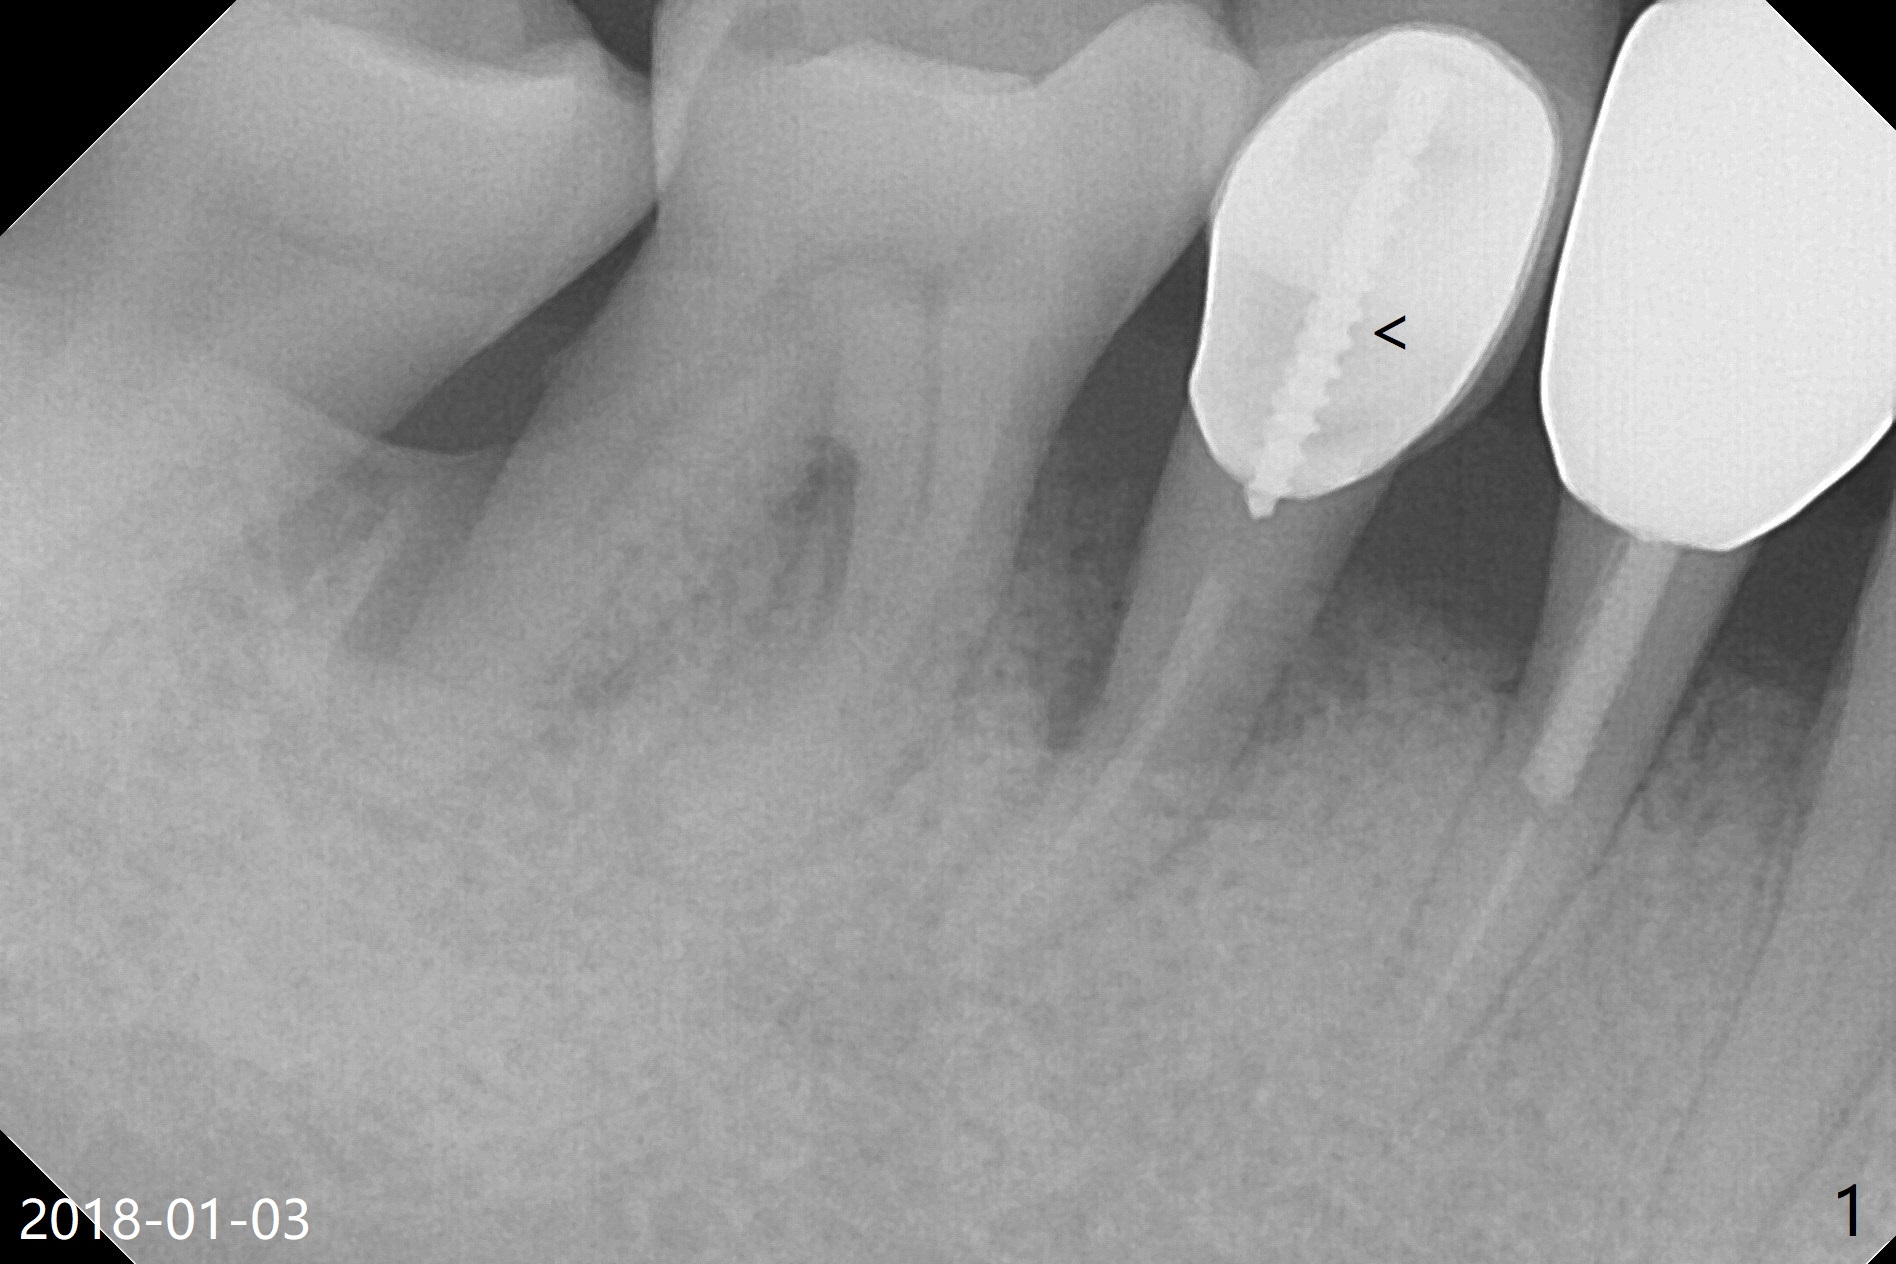

A 47-year-old man cannot chew in the lower right quadrant due to mobility of the tooth #29, which has a post (Fig.1 <). It appears that there is a buccal vertical fracture line. After extraction, osteotomy will be initiated in the mesiolingual aspect of the socket for 7 mm (Fig.2,3). The bone is dense (600-1,000 units); drills are required. Take a PA to confirm the trajectory. Following sequential osteotomy, place a 4x11mm dummy implant before placing a 4x9 or 11 mm definitive one, depending on bone resorption in the last 6 months (compare Fig.2,3 vs. 1).